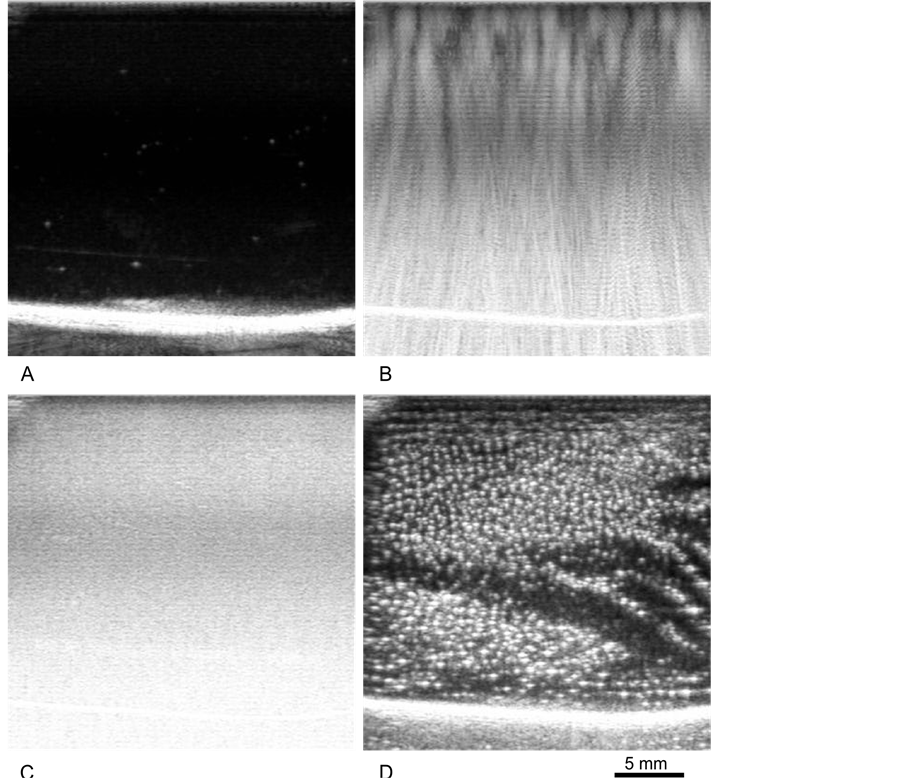

Figure 3. Images obtained using 14 MHz contrast enhanced imaging during unfocused treatment of 10% gel. The magnification for all frames is indicated by the scale bar in (D). Prior to sonication, gel is mainly clear (A). When the high power ultrasound is initially turned on, strong signal is observed from the ultrasound scattered from container walls (B). After a few seconds, the scatter increases dramatically and becomes less coherent (C). After turning off the high power ultrasound, imaging reveals a large number of bubbles remaining in the gel (D).

ultrasound is turned off and begin to rise to the surface, while those in viscous media (10%, 20% gel) almost immediately stop moving and remain fixed, although they will dissipate over 24 hrs. The cavitation thresholds observed when treating the gels with the planar transducer are shown as a function of gel viscosity in Figure 4, with error bars indicating uncertainty in the nominal transducer power. The gray regions indicate the limits of transducer output. The threshold appears to increase almost linearly with the log of viscosity. In general, reducing the duty cycle resulted in higher cavitation thresholds. For this reason, all data shown from this unfocused transducer are at 100% duty cycle, which allowed successful interrogation of most of the samples. Even so, the 30% gel cavitation threshold was not breached by the transducer device, which has a maximum nominal output of 2.4 W/cm2 (2.2 ± 0.1 W/cm2 calibrated intensity). In contrast, both the water and the 5% gel solution were immediately cavitating at the lowest power setting of the system, 0.19 ± 0.01 W/cm2 calibrated intensity.